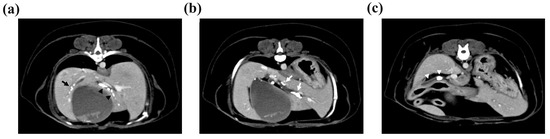

Abdominal radiography revealed radiopaque material suggestive of cholelithiasis in the liver, GB, and CBD area. Ultrasonography (US) showed a mucocele in the GB (Figure 1a) and hepatolithiasis in the left medial, quadrate, and right liver lobes and the GB (Figure 1b,c). The intrahepatic bile duct was dilated with a diameter of approximately 3.3 mm. Distal CBD dilatation was not observed.

Figure 1. Ultrasonographic imaging showing an enlarged gallbladder (GB) (a) due to a GB mucocele and cholelithiasis. The surrounding tissue’s echogenicity was increased, and a small amount of free fluid was also observed. (b) The quadrate liver lobe’s hepatic duct was mostly filled with cholelithiases (white arrows) and dilated to 4.2 mm. (c) Cholelithiasis was also confirmed in the right liver lobe’s hepatic duct (yellow arrows), but hepatic duct dilatation was not observed. Two cholelithiases were also observed inside the common bile duct, which was dilated to 3.7 mm.